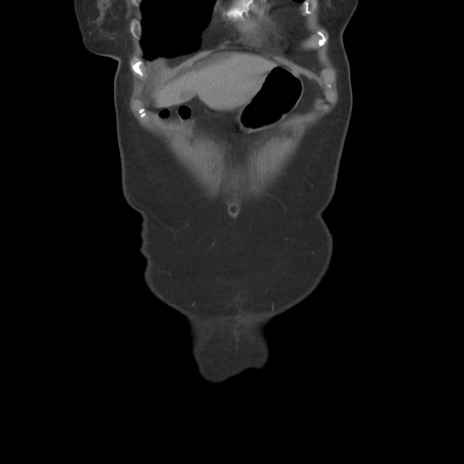

横断像

【症例】80歳代女性

【主訴】下腹部痛

【現病歴】約8時間前より下腹部痛の出現あり、救急外来受診。

【既往歴】両側付属器切除

【身体所見】意識清明、下腹部正中に手術痕あり、その部位に一致して圧痛と反跳痛あり。腸蠕動音は亢進。

【データ】WBC 9300、CRP 0.15